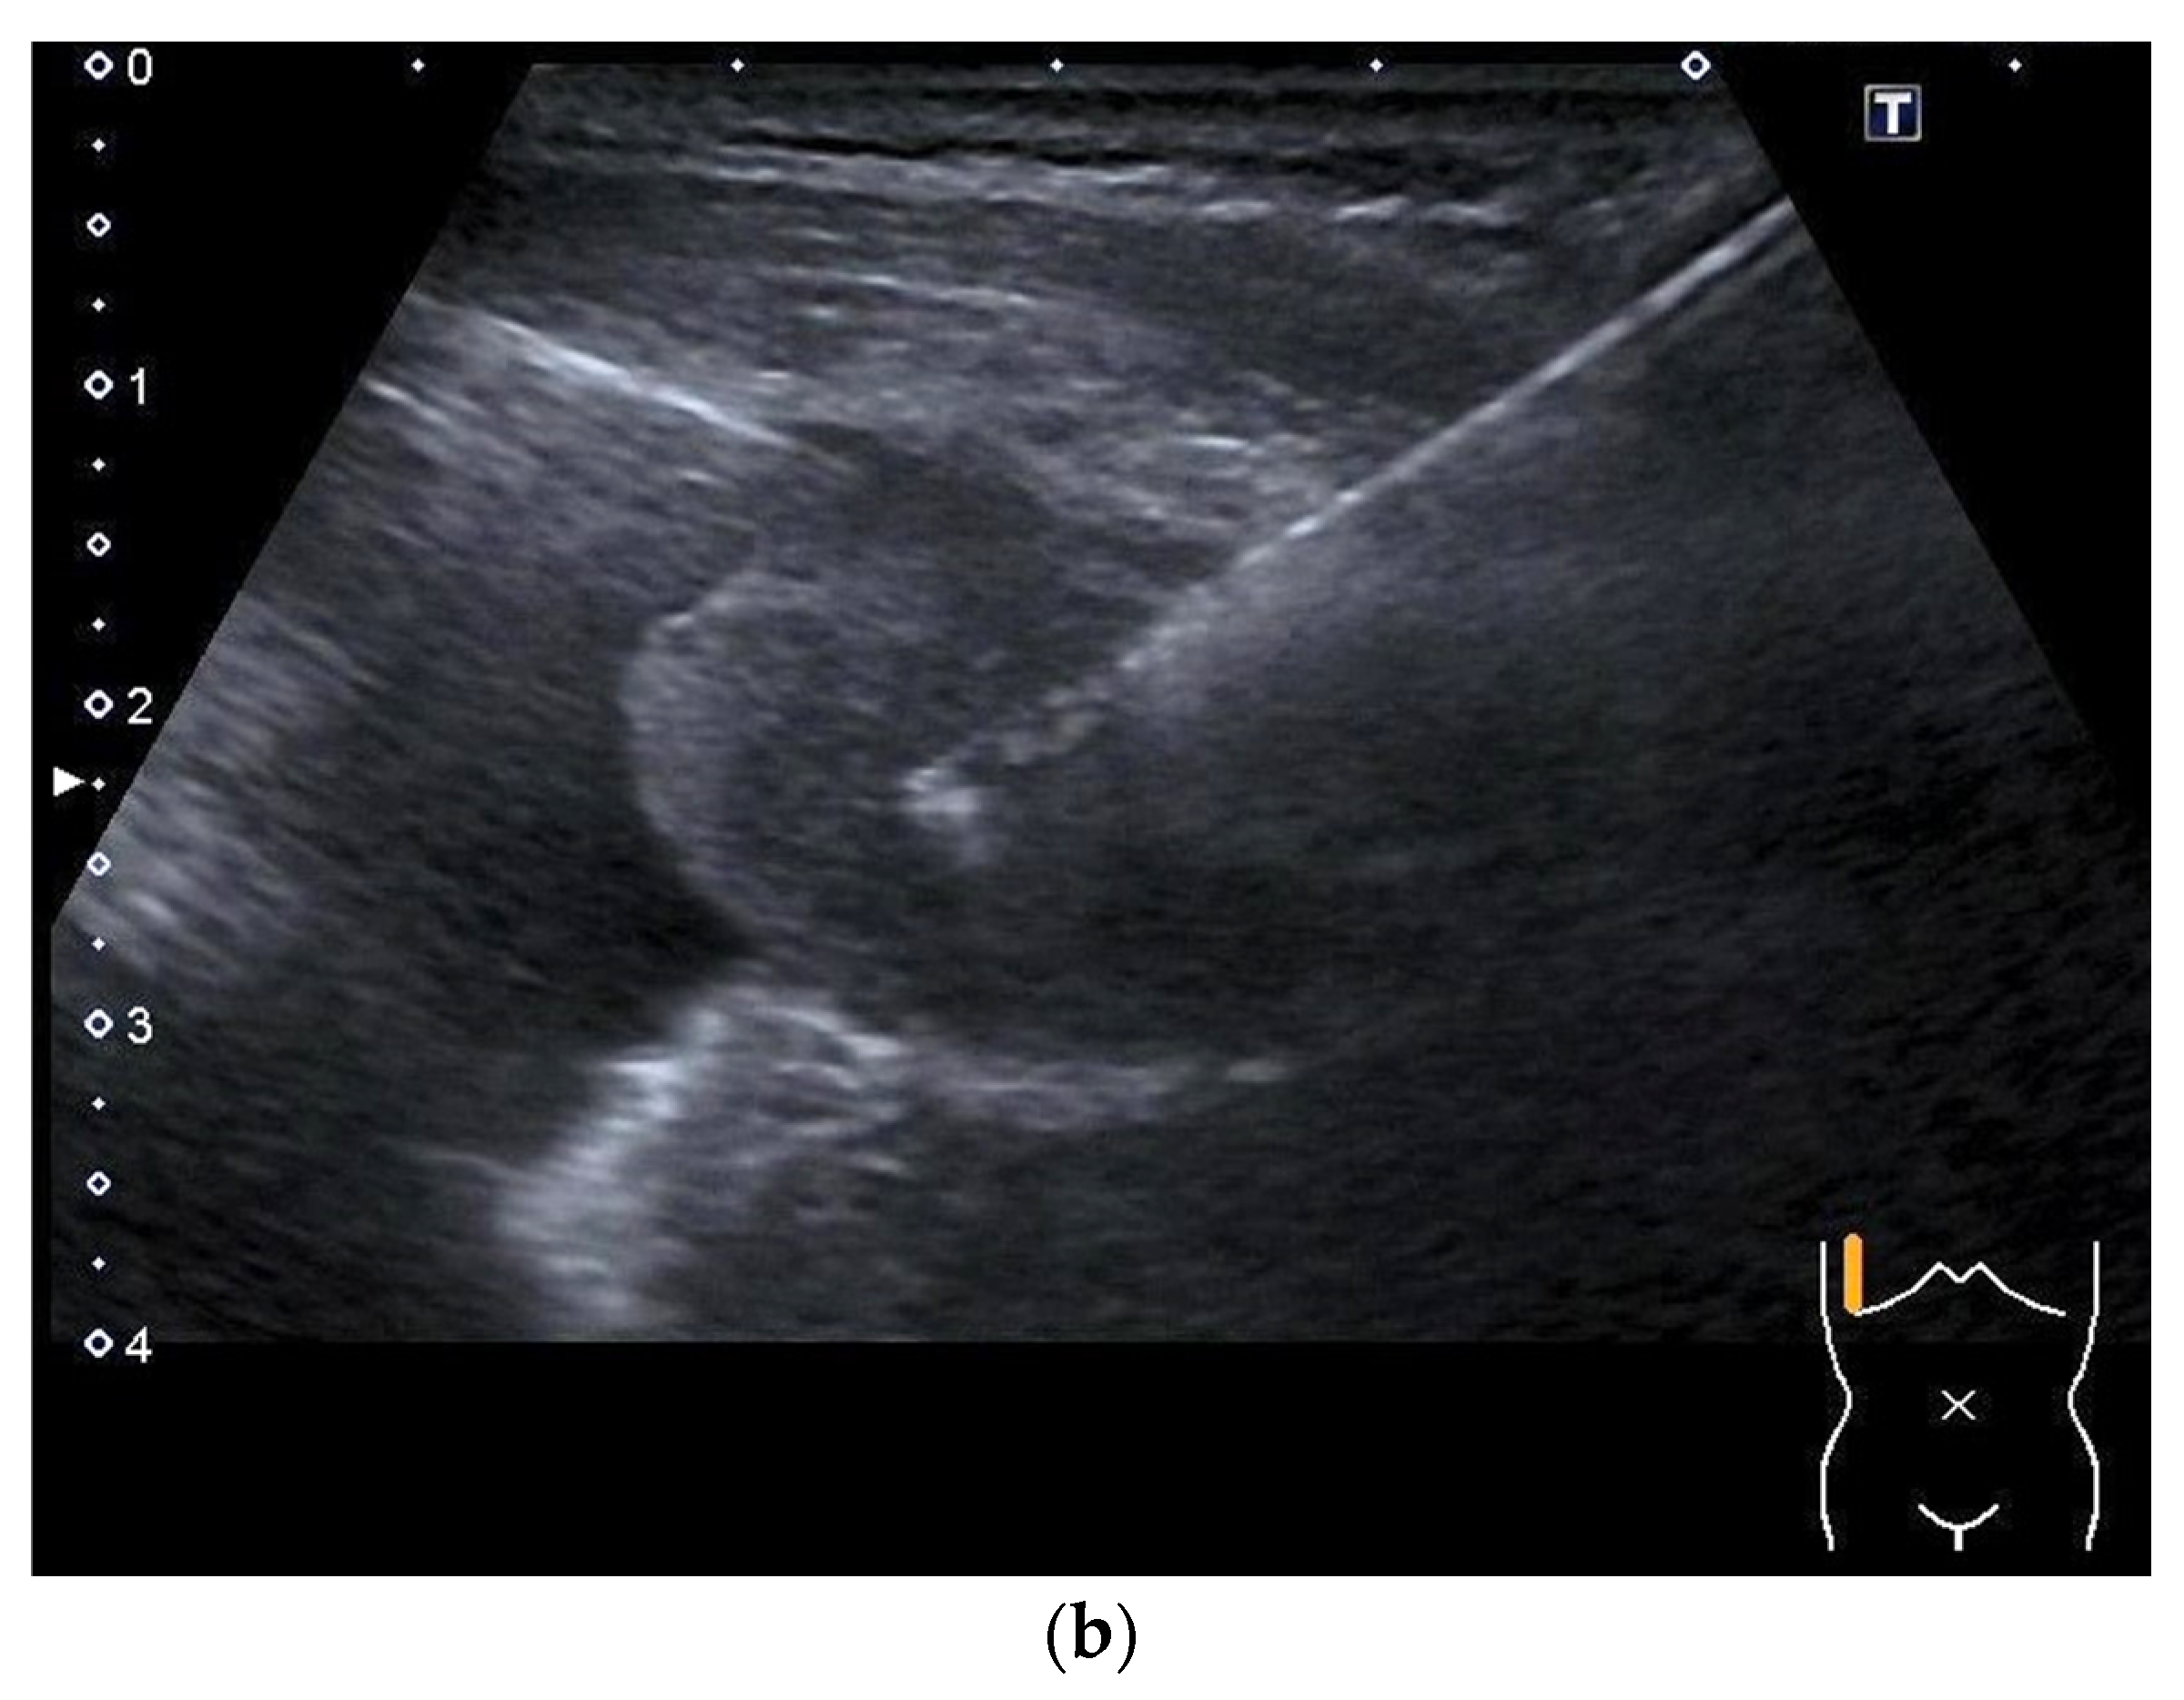

2. Primary Pulmonary Sarcomas